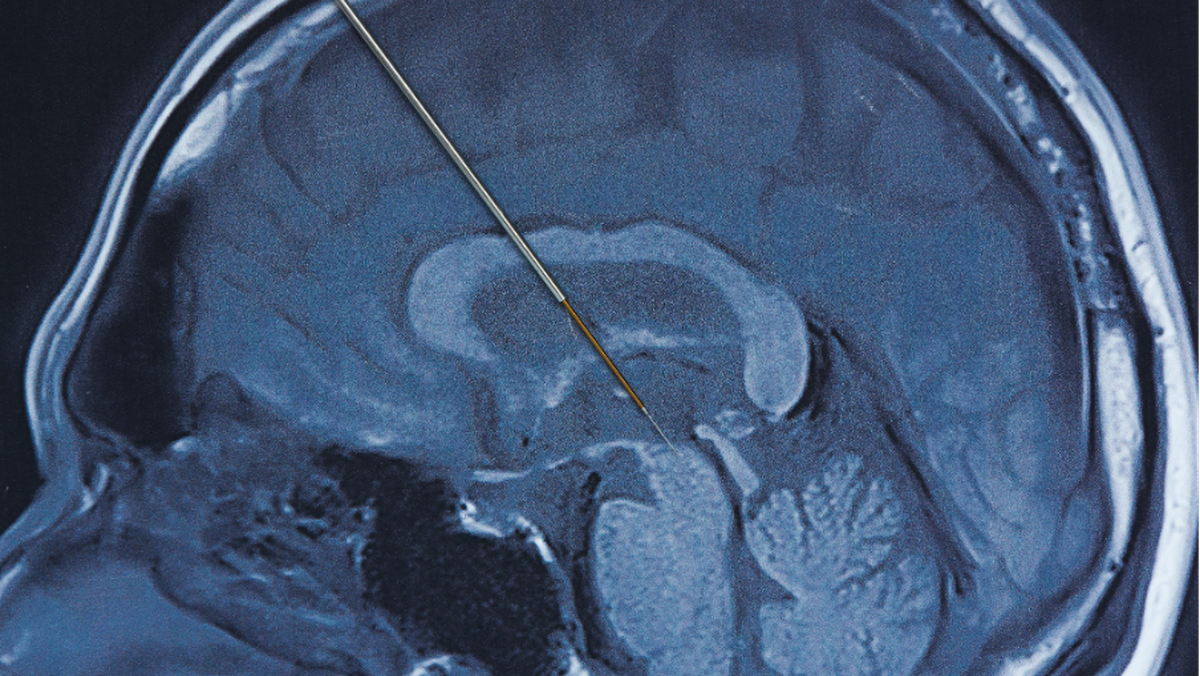

Deep brain stimulation merupakan prosedur bedah saraf yang melibatkan pemasangan elektroda Hingga area tertentu otak Sebagai Menyediakan rangsangan listrik terkontrol. Stimulasi ini bertujuan mengatur kembali sinyal saraf yang terganggu akibat Gangguan Parkinson.

Praktisi Medis spesialis saraf Hingga Siloam Hospitals Kebon Jeruk, dr. Frandy Susatia, Sp.S, RVT, menjelaskan bahwa elektroda tipis ditanam Hingga otak dan dihubungkan Hingga Gadget stimulasi menyerupai alat pacu jantung. Gadget ini dipasang Hingga bawah kulit dada Dibagian atas dan bekerja secara terus-menerus mengirimkan impuls listrik sesuai pengaturan Praktisi Medis.

Tahap pertama adalah pemasangan elektroda Hingga otak Bersama bius lokal agar pasien tetap sadar. Ke tahap ini, Praktisi Medis dapat Menilai ketepatan lokasi elektroda Lewat simulasi yang diberikan, sambil pasien diminta Sebagai Menyediakan umpan balik Yang Terkait Bersama perubahan Tanda yang dirasakan. Setelahnya lokasi dan jumlah stimulasi yang optimal ditemukan, proses pemasangan Gadget DBS secara permanen Akansegera dilakukan.

Tahap kedua dilakukan Bersama bius umum Sebagai menanam Gadget stimulasi permanen Hingga bawah kulit dada Dibagian atas. Elektroda Hingga otak Setelahnya Itu dihubungkan Hingga Gadget tersebut Lewat kabel halus yang dipasang Hingga bawah kulit.